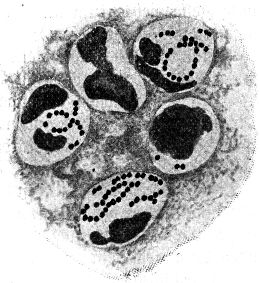

Ein halbes Jahrhundert später erst gelang es den geschickten Händen Antony van Leeuwenhoeks, kleine Linsen so sorgfältig und gleichmäßig zu schleifen, daß sie alle bis dahin angefertigten an Vergrößerungskraft übertrafen; er vervollkommnete hierdurch und durch kleine anderweitige Kunstgriffe seine optische Ausrüstung in bisher noch nicht dagewesenem Maße und untersuchte nun – von Haus aus ohne jede naturwissenschaftliche Ausbildung – mit ihrer Hilfe allerhand Flüssigkeiten: Regenwasser, Pflanzenaufgüsse, Darminhalt von Tieren und Menschen, den eigenen Speichel u. a. m. mikroskopisch.[3] Überall fand er – bald reichlicher, bald spärlicher – kleinste, vollkommen farblose »Tierchen«, die verschieden gestaltet, zum Teil lebhaft beweglich waren. Dank einer vorzüglichen Beobachtungsgabe und ebenso großer Zuverlässigkeit beschrieb Leeuwenhoek diese »Tierchen« so genau, daß wir sie heute mit Sicherheit als Bakterien wiedererkennen können. Auch gab er durchaus naturgetreue Abbildungen von ihnen, die die drei Hauptformen der Spaltpilze vollkommen richtig darstellen: alle die unzähligen Bakterien, die seitdem beobachtet worden sind, lassen sich ihrer Gestalt nach in kugelförmige (Mikrokokken), stäbchenförmige (Bazillen) und schraubenförmige (Spirillen) scheiden (s. Abb. 1). Freilich wechseln sie nach Dimensionen und kleinen Einzelheiten ihres Baues, wie wir sehen werden, in mannigfaltigster Weise, aber alle lassen sich auf einen der drei schon von Leeuwenhoek unterschiedenen Grundtypen zurückführen.

Unter den Lebensvorgängen, die der unmittelbaren Beobachtung zugänglich sind, beansprucht vor allem die Art und Weise der Fortpflanzung unser Interesse. Gerade ihre zuverlässige Beobachtung ist durch die Kochsche Isolierungsmethode außerordentlich erleichtert worden, wenn auch schon vor Koch vielfach richtige Ansichten über die Art und Weise, wie die oft enorme Vermehrung[17] von Bakterien im einzelnen zustande kommt, gewonnen worden sind. Die Vermehrung der Bakterien erfolgt auf eine sehr einfach erscheinende Weise durch Spaltung. Der Mikrokokkus, das Kugelbakterium, das sich zur Teilung anschickt, zeigt eine langsame Vergrößerung einer seiner Achsen, dann eine Einschnürung in der Mitte und endlich eine vollkommene Abschnürung von zwei neuen Tochterkugeln. Ganz analog ist der Teilungsvorgang bei Stäbchen- und Schraubenbakterien, die nach anfänglichem Längenwachstum durch Querteilung in zwei Tochterindividuen zerfallen (vgl. Abb. 6).